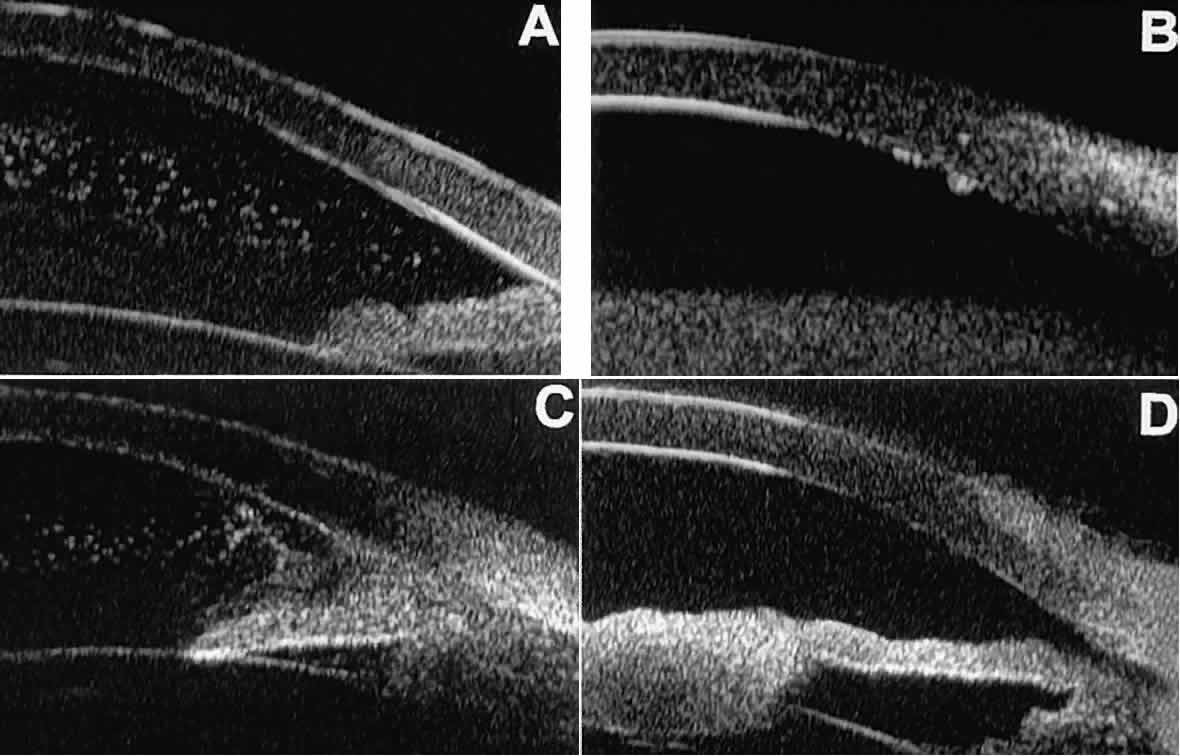

Ultrasound biomicroscopy has also been used to evaluate several anterior scleral disorders,11 including nodular anterior scleritis and scleral hyaline plaques (Fig. 16). On UBM, nodular anterior scleritis (see Fig. 16A) appears as a localized thickening and altered reflectivity of the inflamed sclera. In diffuse non-necrotizing anterior scleritis (see Fig. 16B), UBM shows generalized pronounced thickening of the sclera in the region of involvement. In contrast, after a bout of necrotizing anterior scleritis, UBM can show thinning of the damaged sclera (see Fig. 16C). In eyes with one or more scleral hyaline plaques (see Fig. 16D), UBM shows the lesion to be a highly sonoreflective plate located just anterior to the insertion of the medial or lateral rectus muscle; the lesion has well-defined margins and is so sonoreflective that it shadows the underlying layers of the eye wall.

Fig. 16. UBM features of anterior scleral disorders. A. Nodular anterior scleritis appears as fusiform thickening of limbal sclera. Note apparent lamellae of heterogeneous reflectivity within region of thickening. B. Diffuse anterior scleritis appears as nonfocal scleral thickening in region of inflammation. C. Scleral thinning subsequent to necrotizing anterior scleritis. Note underlying vitreous cells. D. Scleral hyaline plaque appears as dense, hyper-reflective plate several millimeters from horizontal limbus; dense lesion “shadows” deeper tissues.